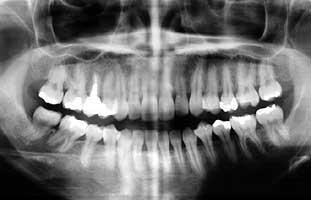

先生に相談なのですが、左上6番・5番の歯(中学生の時くらいに治療して両方インレ

ーを詰めてました)が去年の冬くらいから歯か歯茎か分からないのですが痛み出し、始め

は何ヶ月かに1度月経の時に、それが1ヶ月に1度・週1・毎日と痛みが増していき、今

通っている歯科医院の先生に9月初めに1本ずつ治療してもらいました。5番目の治療は

順調に終わりました。6番のインレーを取ってみたら中で大きな虫歯が出来てたそうです。

新しいインレーを詰めるため仮封した1週間は何も痛みなかったんですがインレーを詰め

た翌々日から特に夜、毎日ジーーーンと大きな痛みがありもしやと思いその週に先生に言

ったところ「深かったからなー歯髄炎かなー」と・・・私は神経を抜きたくなかったので、

「もう一度仮封して様子を見てインレーを詰めて下さい」と言いました。が、翌日から小

さな痛みが毎日あります。水やお湯にしみる事はないのですが、神経を抜かないとダメで

しょうか・・・